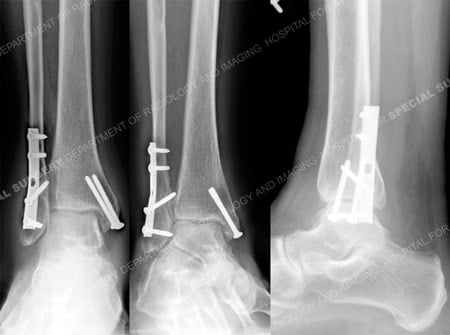

A 50-year-old female fell approximately 3 feet from a step ladder. She presented to the HSS Orthopedic Trauma Service with a bimalleolar ankle fracture placed in a cast by the referring hospital. Open Reduction and Internal Fixation (ORIF) was performed by Dr. David L. Helfet with placement of a plate and multiple screws, including an interfragmentary lag screw, for the fibula fracture and 2 screws for fixation of the medial malleolus fracture. She returned at regular follow-up intervals and healed uneventfully and at 8 months following surgery radiographs illustrated a healed ankle fracture and clinically she reported no pain and a full return to pre-injury activities.

X-rays taken at 9 months revealing a healed ankle fracture.